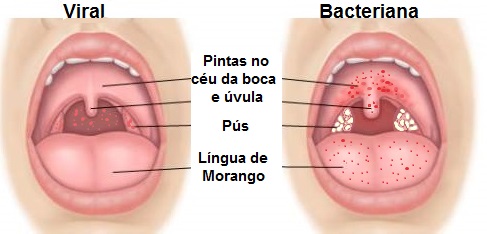

“Infecções virais, como gripes e resfriados, são a causa mais frequente de dor de garganta, enquanto a amigdalite bacteriana, menos comum, pode apresentar pontos de pus e febre alta.”

Infecções Virais e Bacterianas: O Duelo na Garganta

As infecções virais, como as do resfriado comum e da gripe, são as vilãs mais comuns. Elas costumam vir acompanhadas de outros sintomas, como coriza e tosse. Já as infecções bacterianas, como a estreptocócica, embora menos frequentes, exigem atenção especial, pois podem levar a complicações se não tratadas corretamente com antibióticos. A diferenciação é crucial para o tratamento.

Qual a diferença entre dor de garganta viral e bacteriana?

A dor de garganta viral geralmente vem acompanhada de outros sintomas como coriza e tosse, e melhora com repouso e hidratação. Já a dor de garganta bacteriana costuma ser mais intensa, com febre alta, dor ao engolir e, às vezes, presença de pus. Saber diferenciar é o primeiro passo para o tratamento correto.